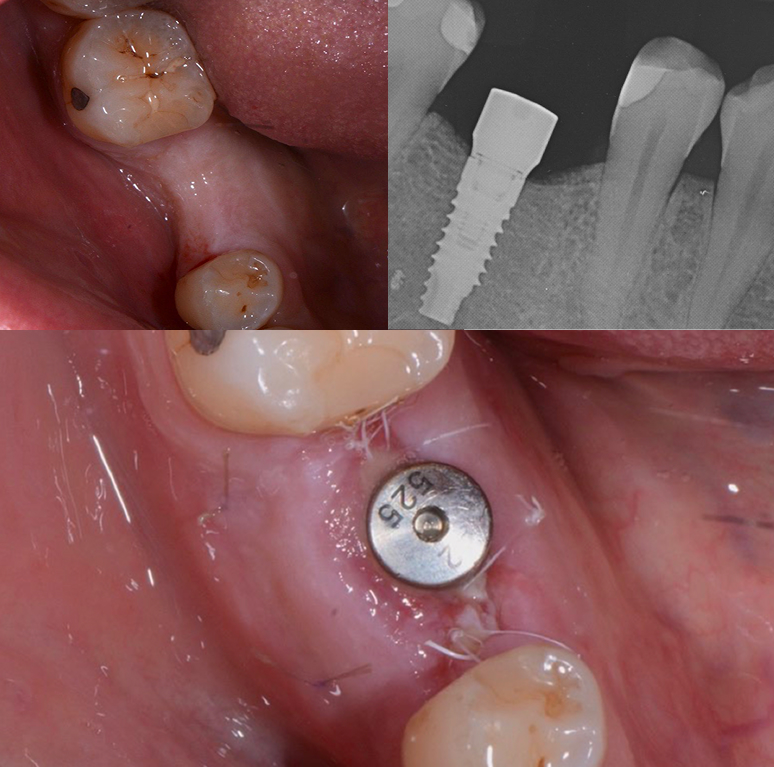

La rigenerazione ossea è una delle specialità che richiede grande impegno e esperienza. Questo tipo di intervento necessita di una combinazione di competenze avanzate, l’utilizzo di materiali biocompatibili altamente specializzati e l’adozione di protocolli terapeutici rigorosamente sperimentati e collaudati.

La rigenerazione ossea offre la possibilità di salvare denti gravemente compromessi che altrimenti dovrebbero essere estratti, evitando la necessità di sostituirli con impianti dentali. Inoltre, gli impianti stessi, in caso di atrofia ossea o perdita significativa di volume osseo, possono necessitare di interventi di rigenerazione ossea per garantire il loro posizionamento sicuro e stabile. In questi casi, la rigenerazione ossea è fondamentale anche per ottenere risultati estetici ottimali, assicurando un sorriso armonioso e naturale.